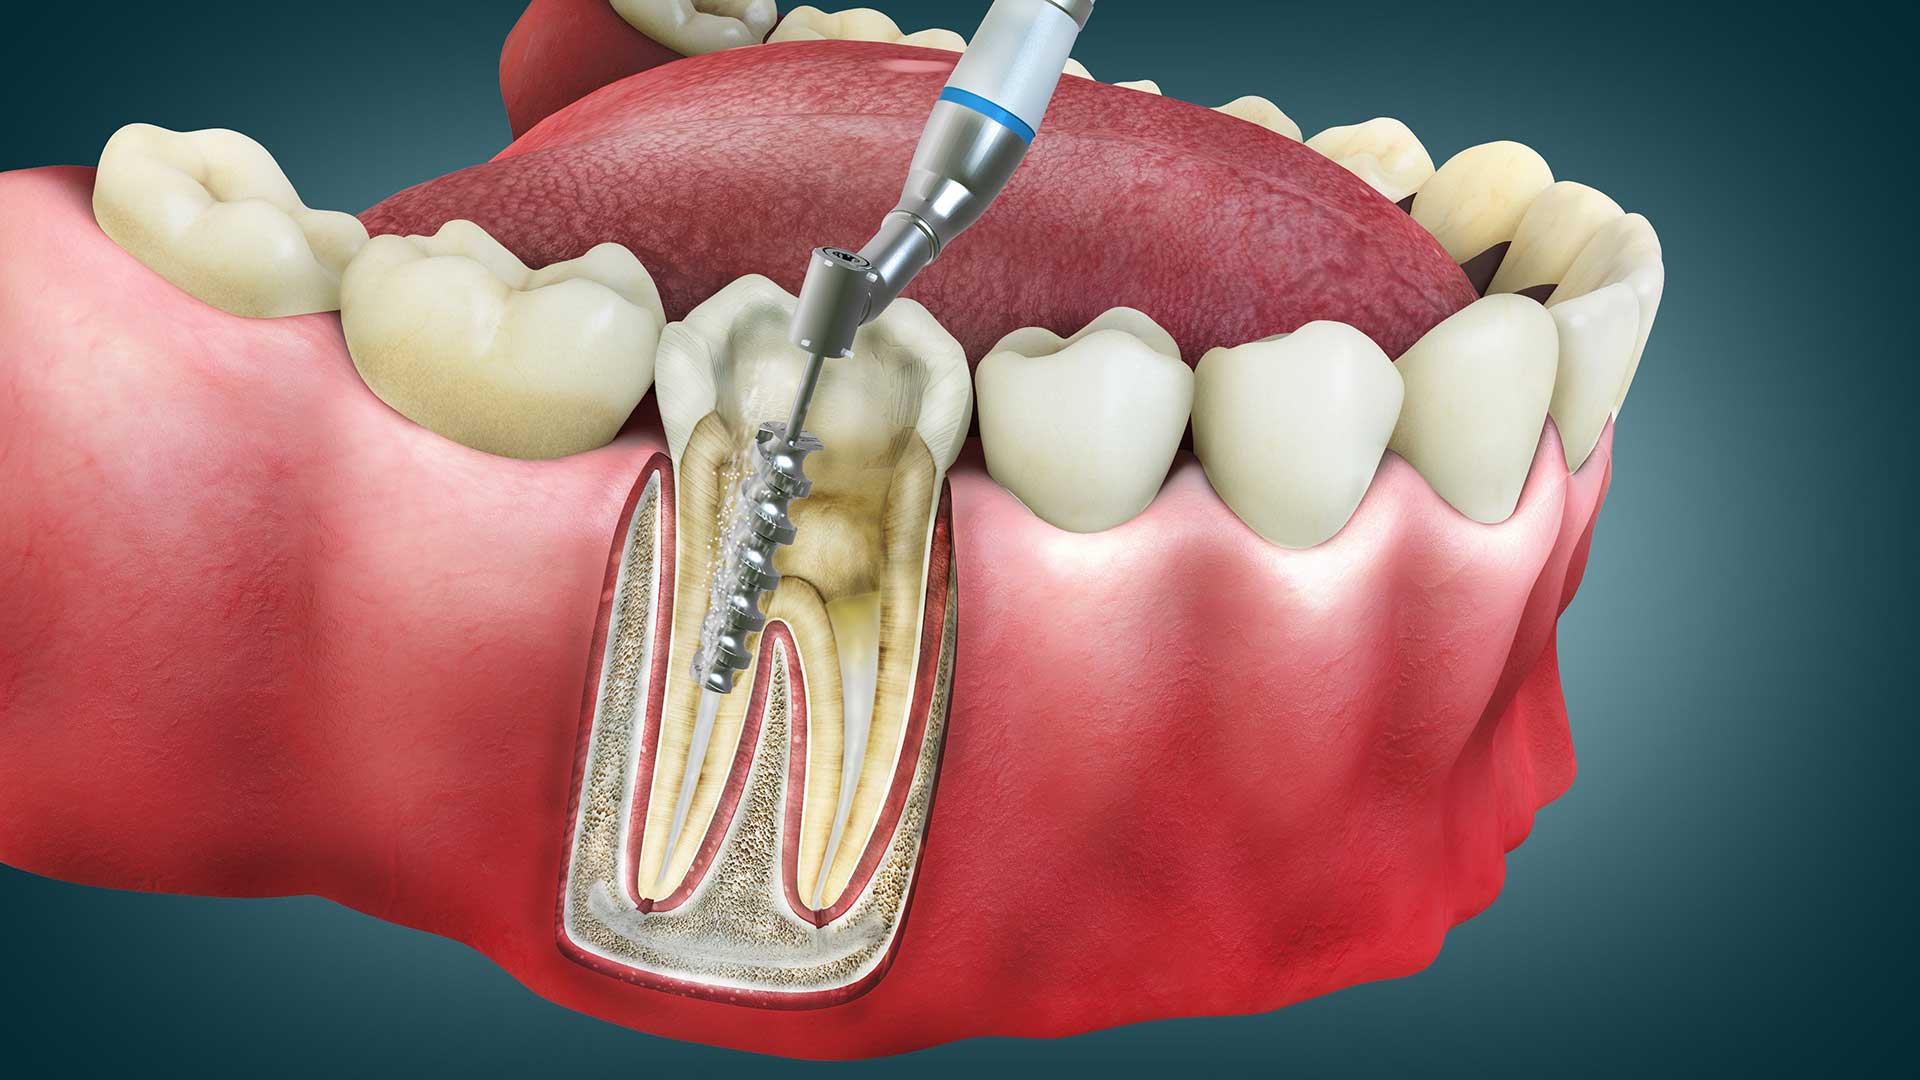

Root Canal Treatment (RCT)

A Root Canal Treatment (RCT) is a painless and effective procedure used to save a severely decayed or infected tooth. It removes the infected pulp, cleans the inside of the tooth, and seals it to prevent further infection.

Steps in Root Canal Treatment

🦷 Step 1: Diagnosis & X-ray – The dentist examines the tooth and takes an X-ray to assess the infection.

🦷 Step 2: Numbing & Pulp Removal – Local anesthesia is applied, and the infected pulp (nerves & blood vessels) is removed.

🦷 Step 3: Cleaning & Shaping – The inside of the tooth is cleaned, disinfected, and shaped.

🦷 Step 4: Filling & Sealing – The tooth is filled with a biocompatible material and sealed to prevent reinfection.

🦷 Step 5: Crown Placement – A dental crown is placed on the tooth for strength and protection.